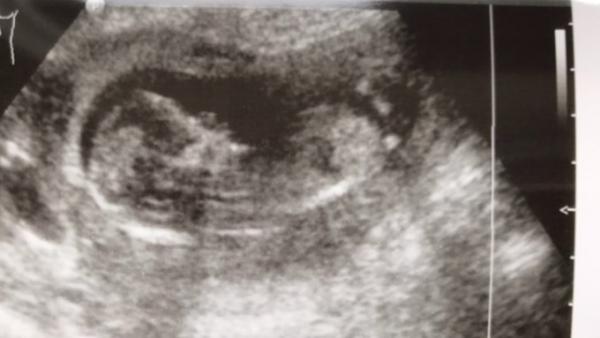

Hallo ihr lieben, Ich habe ein Bild von 13+3. vielleicht kennt sich hier jemand aus und kann anhand des Bildes den Nub erkennen. Ich wäre über ganz viele Antworten dankbar.

Hier das bild

Das ist der "Fortsatz",der sich unter dem Einfluss von Testosteron beim männlichen Fötus zum Penis weiterentwickelt und beim weiblichen zur Vagina.In der Frühschwangerschaft sieht das bei beiden noch ziemlich gleich aus,allerdings soll man so ab der 12.Woche (sofern man genug Erfahrung hat) am Winkel,den dieser Fortsatz im Verhältnis zur Wirbelsäule bildet,erkennen können,ob es ein Mädchen oder ein Junge ist.Unter 30 Grad spricht für ein Mädchen,über 30 Grad für einen Jungen.

Ich würde mal auf Mädchen tippen!

Tippe auf Mädchen ![]()